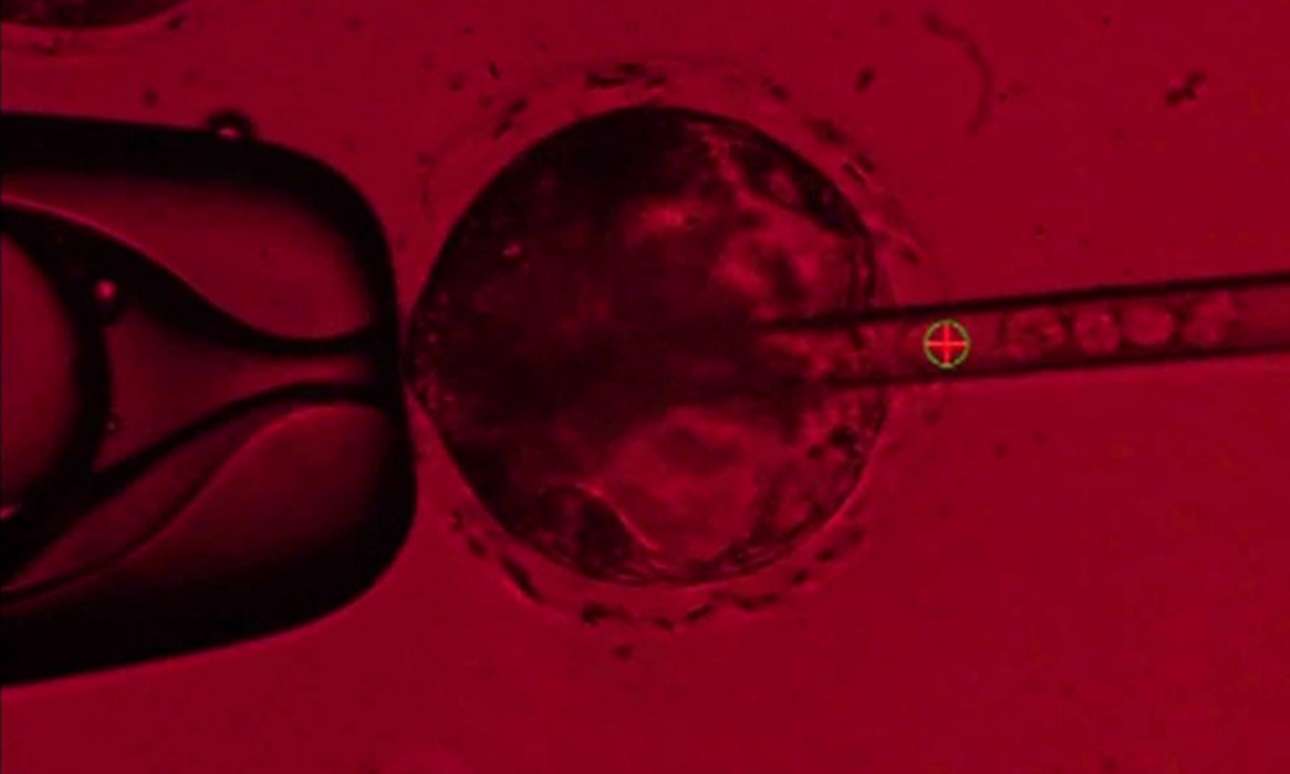

Στο πανεπιστημιακό ερευνητικό κέντρο συνδύασαν ανθρώπινα βλαστοκύτταρα με DNA χοίρων και δημιούργησαν ένα έμβρυο το οποίο άφησαν να αναπτυχθεί για 28 ημέρες. Εν συνεχεία τερμάτισαν το πείραμα για να αναλύσουν τους ιστούς του εμβρύου.